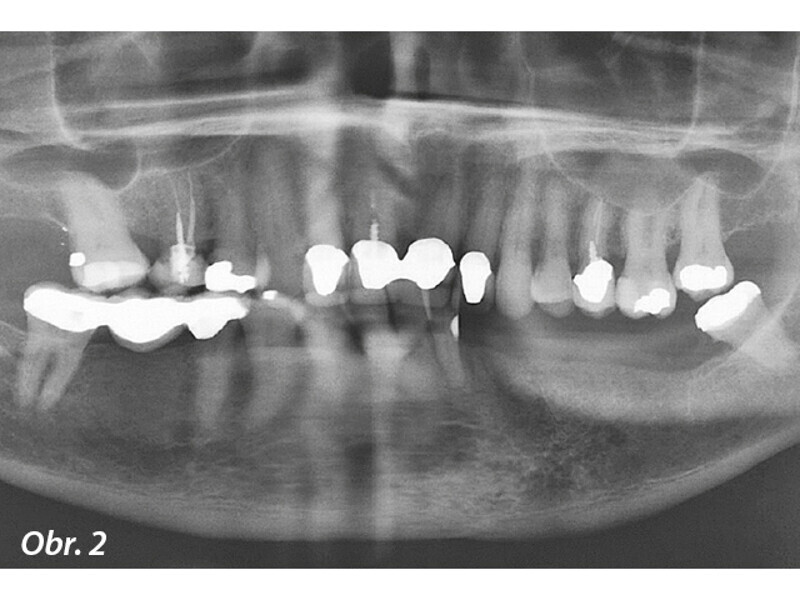

Rekonstrukce chrupu v dolní čelisti